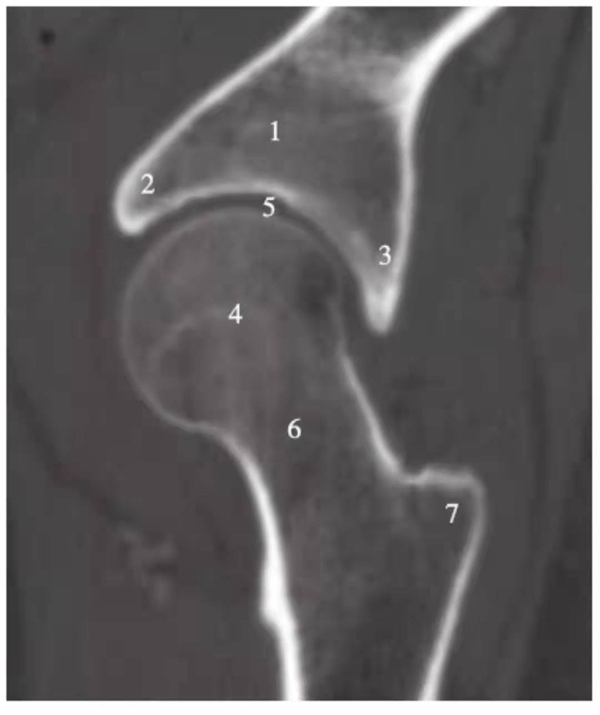

矢状位重建

图8 髋关节矢状位重建

1.髂骨;2.髋臼前唇;3.髋臼后唇;4.股骨头;5.关节间隙;6.股骨颈;7.大转子